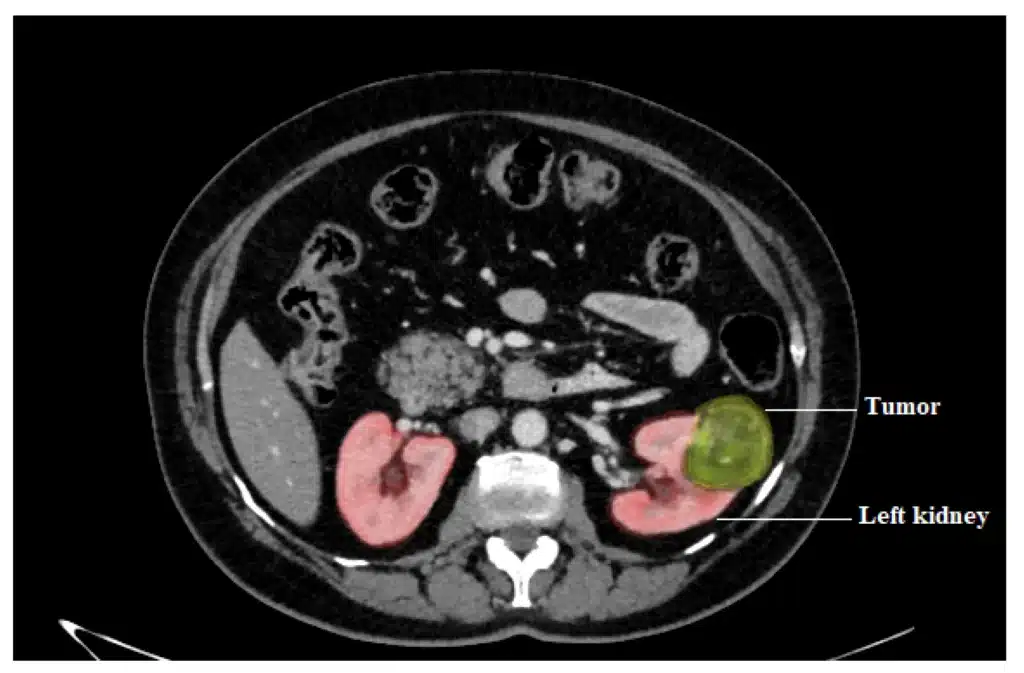

For kidney tumors, the single-port system enables precise excision of the mass while preserving healthy kidney tissue. Most surgeries are performed through a single flank or lower abdominal incision, reducing pain and recovery time.

Left kidney mass for partial nephrectomy

Image showing the kidney mass

CT scan shows the location of the kidney cancer